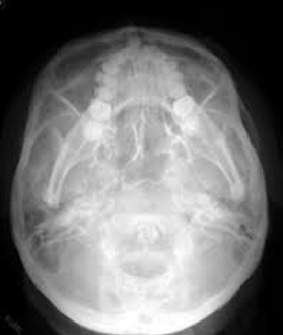

SUBMENTO VERTEX